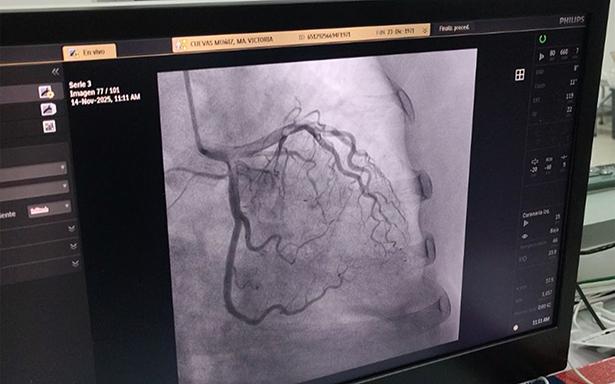

El Instituto Mexicano del Seguro Social (IMSS) en Guerrero realizó la 9ª jornada de hemodinamia en el Hospital General Regional (HGR) No. 1 “Vicente Guerrero”, con el objetivo de fortalecer la atención oportuna y resolutiva para pacientes con enfermedades cardiovasculares, en el marco de la estrategia 2-30-100 que tiene entre sus objetivos incrementar el número de cirugías, consultas de especialidad y de medicina familiar.

Durante esta jornada se brindó atención a 10 pacientes, siete de ellos fueron atendidos mediante procedimientos que permitieron restablecer el flujo sanguíneo y mejorar la función cardíaca a través de la colocación de stents, en tanto tres fueron casos de emergencia que requirieron intervención inmediata.